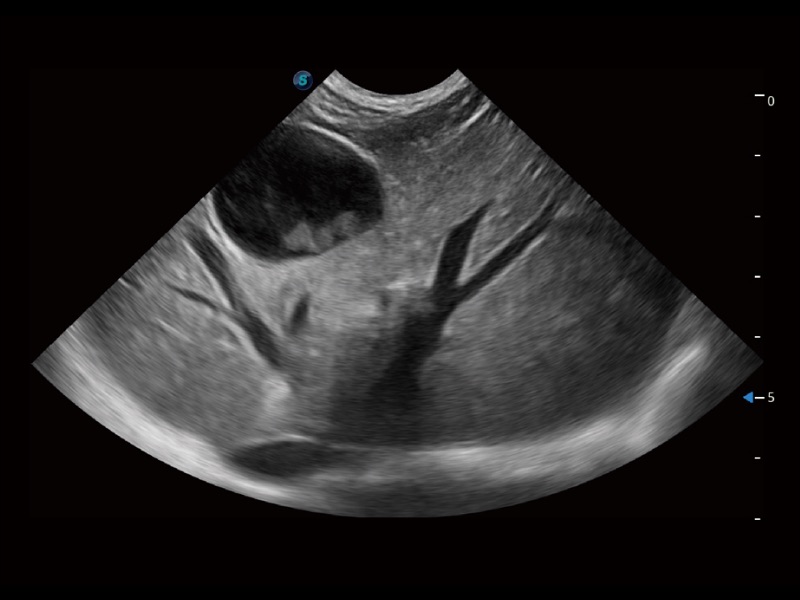

ProPet 70 进一步提升了微米成像算法,更加注重对基础原始图像的还原和保留,在有效减少斑点噪声、增强组织边界显示的同时,避免过度优化丟失真实的解剖信息。

ProPet 70专为动物医生设计,对不同的动物体型和生理结构作出了针对性的优化。通过动物影像专用软件,可满足个性化的应用需求,帮助动物医生获得更精确的诊断数据。